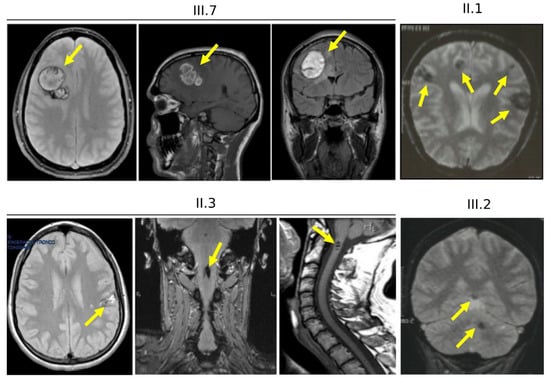

3.4. Clinical Features of Cases Carrying the KRIT1 c.1664C>T Variant (Family 12)

3.6. Clinical Features and Family History of Case #1